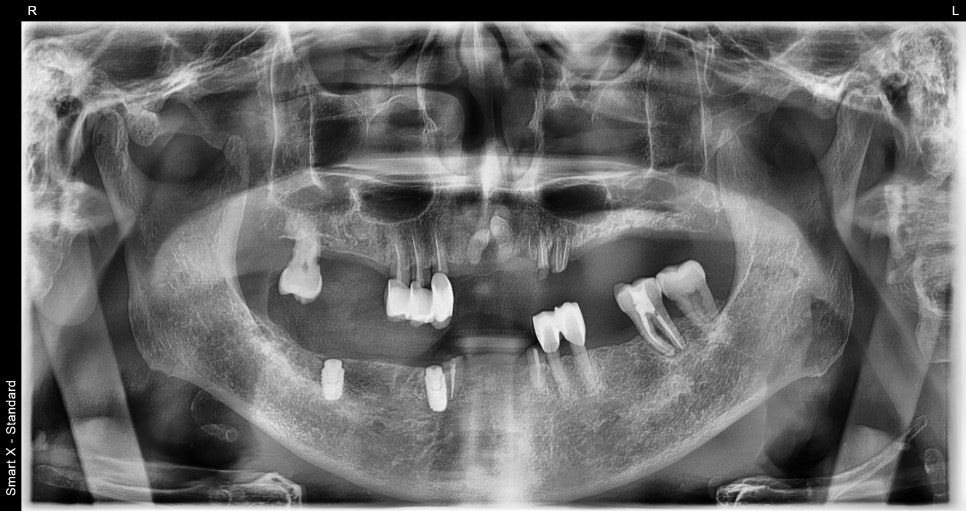

치료 전후 비교

※ 아래 사진은 치료 전후 비교 사진입니다.

– 상악 완전틀니 장착 후 모습

– 하악 임플란트 식립 후 부분틀니 장착 모습

<Before>

<After>